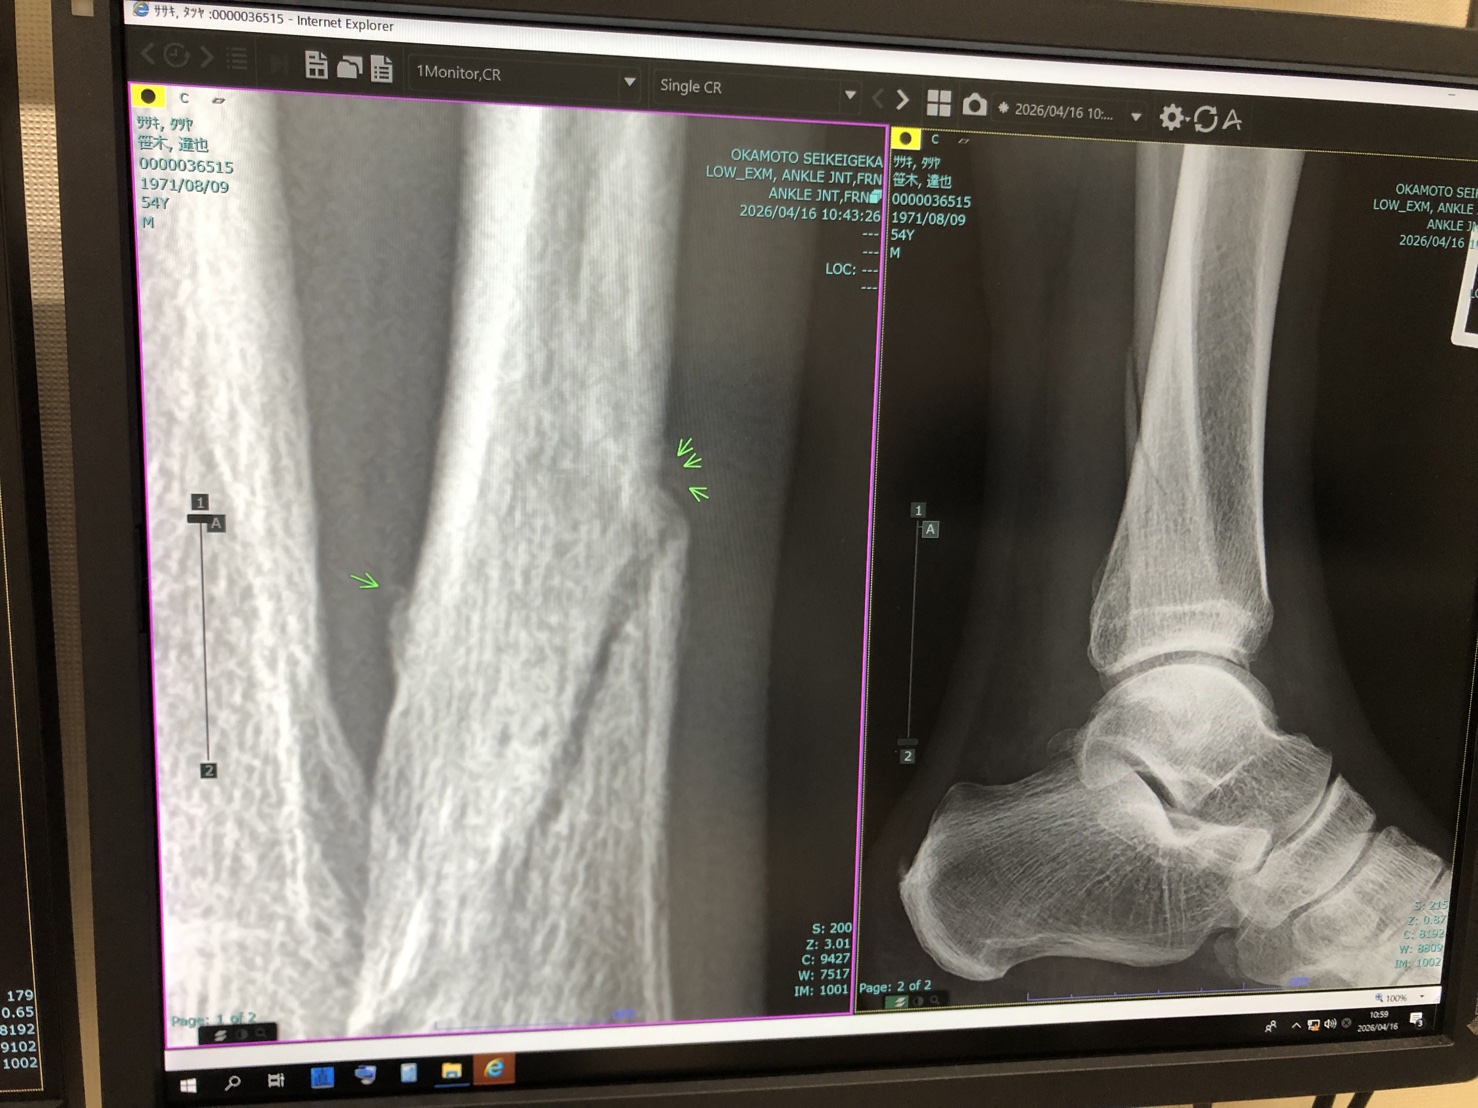

一昨日、医者で撮ったレントゲン写真がコチラ。

「ちょっと時間がかかりましたが、ようやく骨がくっ付いて来ましたね。順調ですよー」